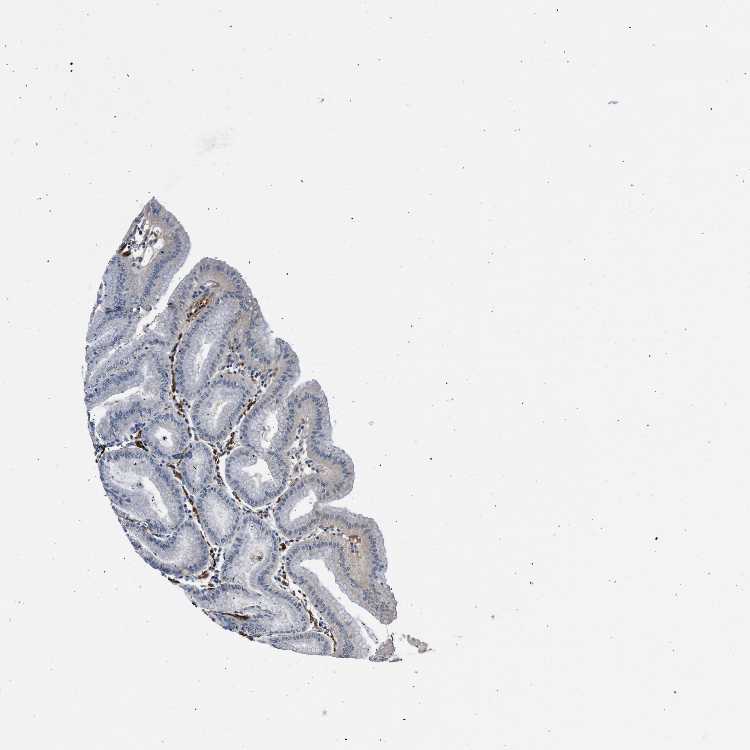

STOMACH 1 - Antibody stainingi

Antibody staining in the annotated cell types in the current human tissue is reported as not detected, low, medium, or high, based on conventional immunohistochemistry profiling in selected tissues. This score is based on the combination of the staining intensity and fraction of stained cells.

Each image is clickable and will lead to virtual microscopy that enables deeper exploration of all samples and also displays staining intensity scores, fraction scores and subcellular localization as well as patient and tissue information for each sample.

Antibody HPA019711Antibody HPA029535

Glandular cells LowNot detected